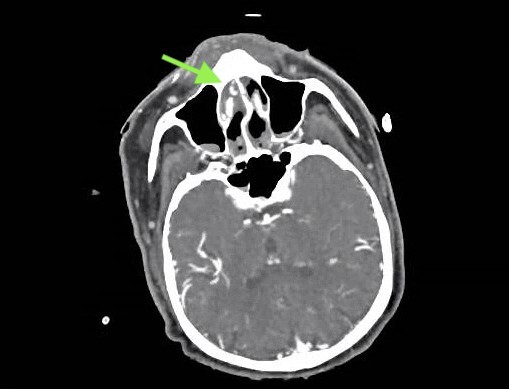

Otolaryngology was consulted and recommended arterial embolization. Several hours later, the patient started developing signs and symptoms of hemorrhagic shock, including a significant drop in blood pressure (74/36), tachycardia with a rate of 118 BPM, altered mental status, tachypnea, cold extremities, and poor urine output. Laboratory values upon admission were significant for a Hemoglobin of 10.3 g/dL (previously 12.6 g/dl two days prior when the patient was discharged from the hospital). Upon admission, the Platelet level was 186 k/uL (previously 106 k/uL two days before the patient was discharged from the hospital). Coagulation studies showed an activated partial thromboplastin time of 34.3 seconds, a prothrombin time of 18.30 seconds, and an international normalized ratio (INR) of 1.6. Two units of packed red blood cells, one unit of prothrombin complex concentrate, and one liter of Lactated Ringers were subsequently administered. Computed Tomography Angiography (CTA) of the neck with IV contrast demonstrated contrast extravasation predominantly within the anterior right nasal cavity, likely arising from Kiesselbach’s complex (Figure 1). Neuroendovascular surgery was consulted, and the patient underwent emergent right facial artery, right internal maxillary artery, and right occipital artery origin coil embolizations. The patient required a total of eleven units of packed red blood cells, units of fresh frozen plasma, one unit of prothrombin complex concentrate, two units of Platelets, and one unit of Kcentra. The patient’s hospital course was further complicated by sequela of his uncontrolled bleeding and subsequent resuscitation, including acute on chronic heart failure exacerbation, iatrogenic optic nerve blindness from emergent arterial embolization, and gangrene of several upper extremity digits. cavity, likely arising from Kiesselbach’s complex (Green Arrow). Stable deformity of the nasal septum with leftward deviation. Right sided nasal balloon tamponade. Debris within the bilateral nasal cavities, nasopharynx, and paranasal sinuses.